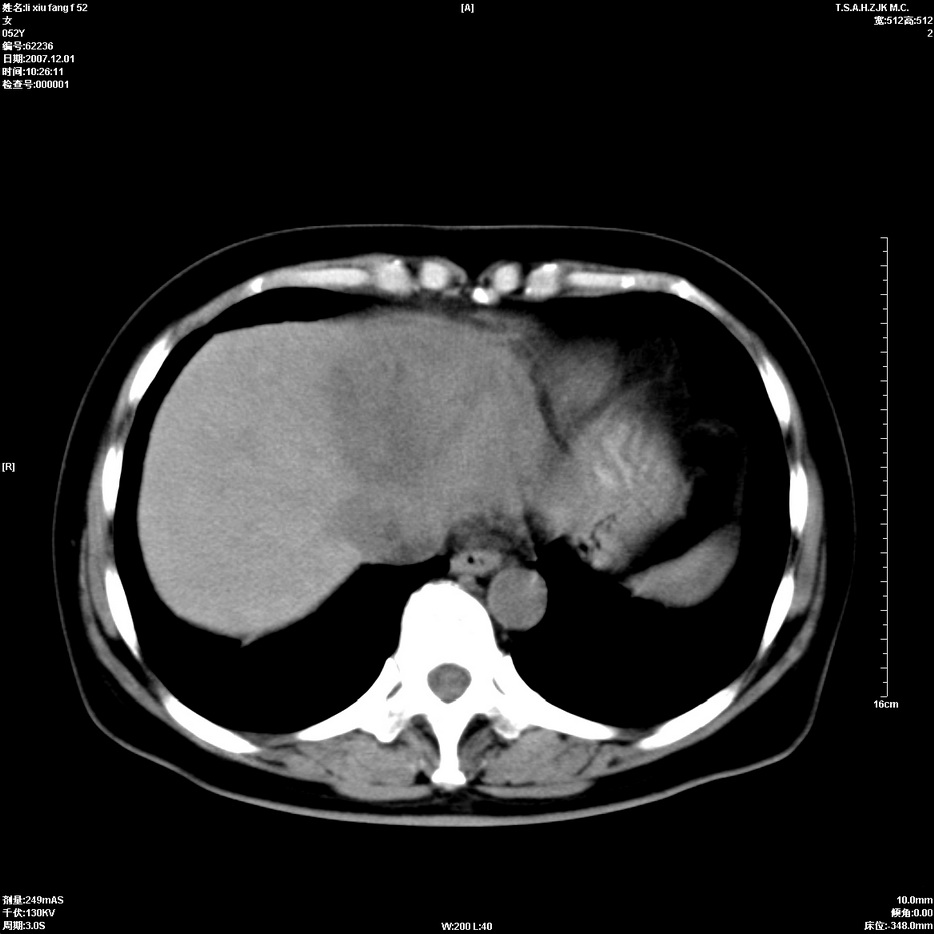

标题: CT12858:女,52岁,胎甲球蛋白861肝左叶占位,肝癌。下腔静 [打印本页]

标题: CT12858:女,52岁,胎甲球蛋白861肝左叶占位,肝癌。下腔静

肝左叶巨大低密度灶肿块,增强符合快进快出表现,有动静脉交通支;静脉期,下腔静脉内有充盈缺损,afp明显升高,支持肝癌并下腔静脉癌栓形成。

以下是引用拾荒者在2008-4-15 22:57:00的发言:[br]肝左叶巨大低密度灶肿块,增强符合快进快出表现,有动静脉交通支;静脉期,下腔静脉内有充盈缺损,afp明显升高,支持肝癌并下腔静脉癌栓形成。